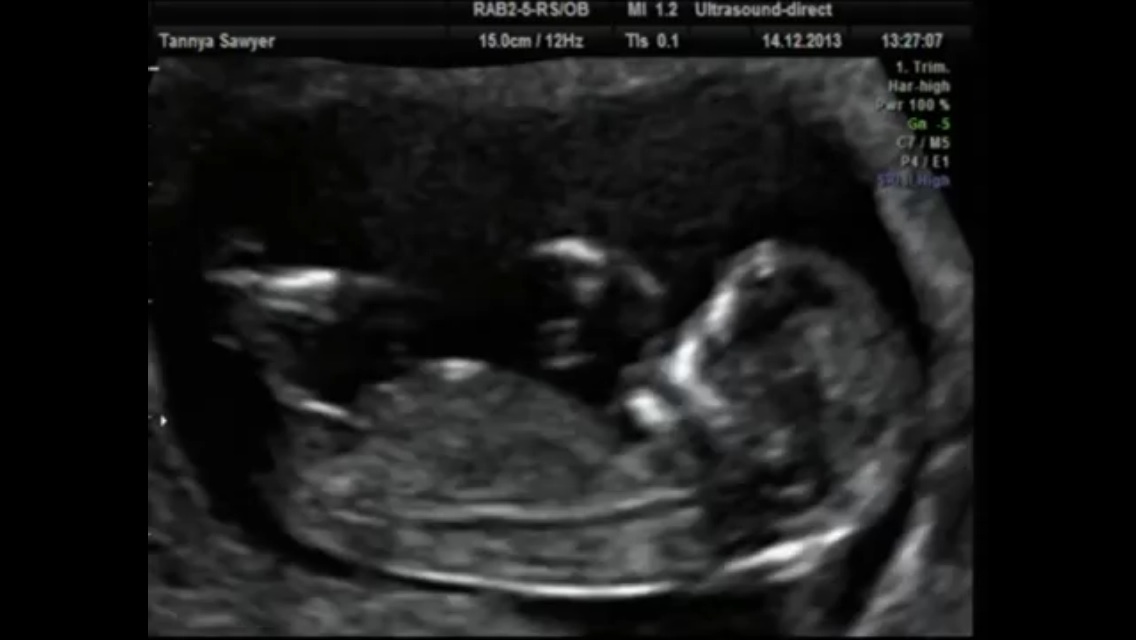

I'm a little early at 12+2 but wondered which you think I am!

It seems to go up ever so slightly at the end of the nub which is the only thing keeping me from guessing more confidently girl but it's flat, in alignment with spine and has that long thin girly shape so I'd say 70-80% girl guess from me!

I think boy. It's got an angle to start and then the end also goes upward again.